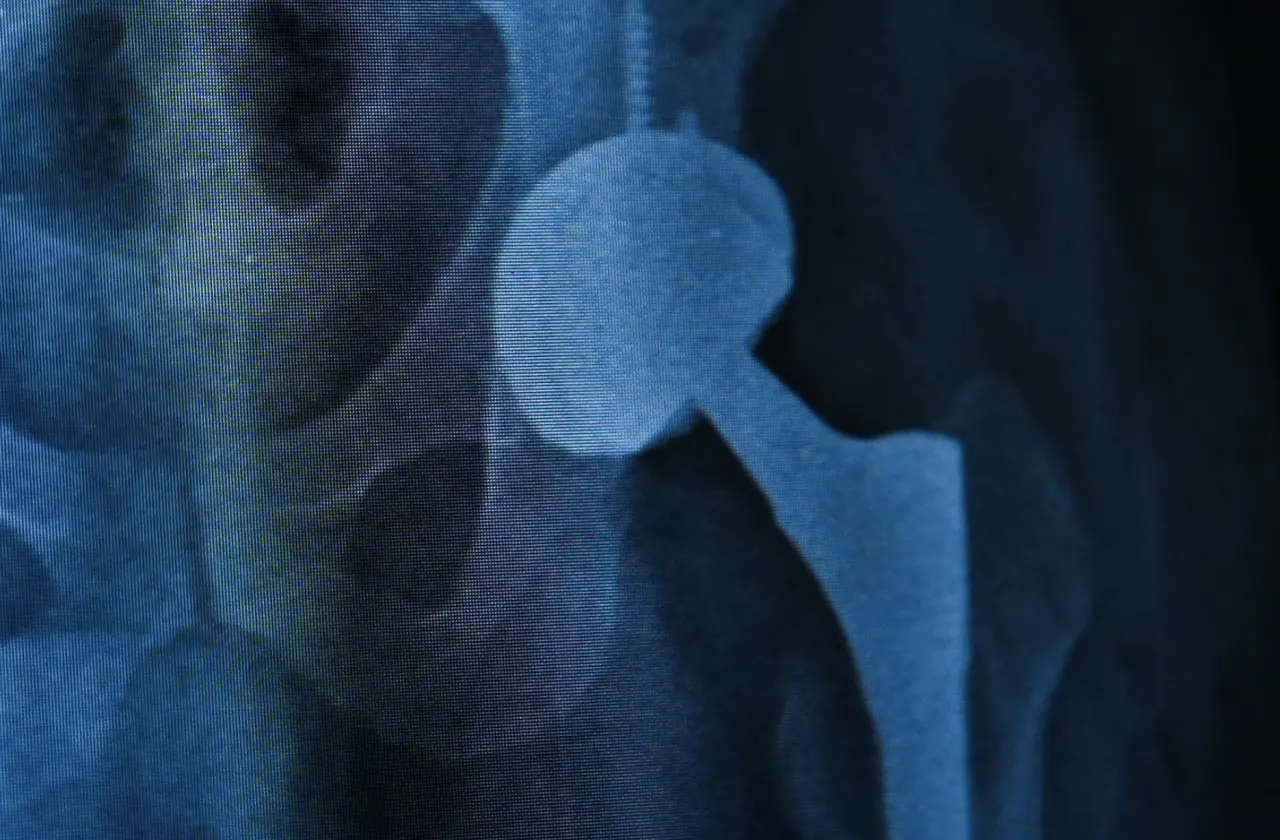

Tekirdağ Ergene'de yaşayan Zafer Aygün için iş kazası sonrası başlayan kalça ağrıları, dört yıl boyunca bitmek bilmeyen bir çileye dönüştü. Farklı hastanelerde ameliyatlar geçirmesine rağmen, kalça protezi etrafındaki enfeksiyon ve protezdeki gevşeme nedeniyle yaşam kalitesi her geçen gün daha da düştü. Aygün, aradığı çözümü Medipol Mega Üniversite Hastanesi'nde buldu. Ortopedi ve Travmatoloji Uzmanı Prof. Dr. İbrahim Azboy'un uyguladığı tek aşamalı kalça protezi değişimi yöntemiyle sağlığına kavuşarak hayatına kaldığı yerden devam etti.

Tedavi süreci hakkında detaylı bilgi veren Prof. Dr. İbrahim Azboy, “Hastamız daha önce protez ameliyatı olmuş ama protezin yerinden çıkması, ardından gevşeme ve çökme sorunları yaşamış. Bu komplikasyonlar üzerine ağrıları devam edince bize başvurdu. Enfeksiyon şüphesiyle yapılan ileri testlerde kalçada ayrıca enfeksiyon tespit ettik. Genelde bu tip durumlarda iki aşamalı cerrahi uygulanır. Bu yöntemde iki ameliyat yapılır. Protez çıkarıldıktan geçici olarak kalçaya çimento konur. İki ay sonra çimento çıkarılıp yeniden protez yerleştirilir. Ancak biz, Zafer beyin protez enfeksiyonunu ‘’Almanya’da geliştirilen tek aşamalı yöntemle tedavi ettik” dedi.

Prof Dr. Azboy sözlerine şöyle devam etti: “Önce enfekte protez çıkarıyor. Daha sonra mekanik debridman denilen yöntemle enfekte dokular etkili bir şekilde temizleniyor. Ardından kimyasal ajanlar kullanılarak iltihaplı bölge dezenfekte ediliyor. Yara geçici olarak kapatılıyor. Tüm setler ve malzemeler dışarı çıkarılıyor. Yeni setler açılıyor. Yeni protez aynı seansta hastaya yerleştiriliyor. Böylece tek ameliyatla hastanın enfeksiyonu tedavi edilmiş oluyor. Böylece hasta kısa sürede ayağa kalkabiliyor, hastanede yatış süresi kısalmış oluyor ve kalça fonksiyonlarını kısa sürede geri kazanıyor. Nitekim, Zafer Bey de ameliyat sonrası hızla yürümeye başladı ve hastaneden kendi aracına kullanarak taburcu oldu.”